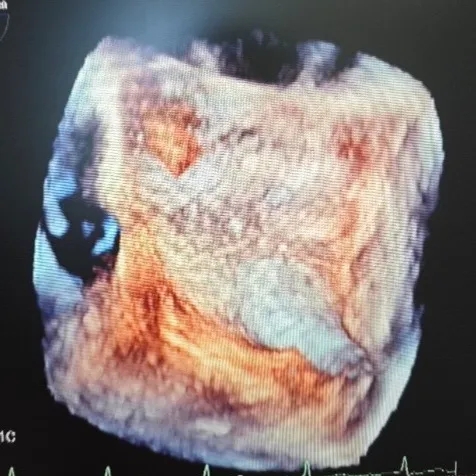

超声所见:经食管超声心动图+灰阶三维成像+彩色三维成像:卵圆孔未闭可吸收封堵器置入术后6个月:可吸收封堵器位置固定,未见残余分流,可吸收封堵器与房间隔自身组织贴合紧密,变薄,其回声与心肌组织回声接近,右房面可见封堵器的条状回声反射。

超声结论:经食管超声心动图+灰阶三维成像+彩色三维成像:卵圆孔未闭可吸收封堵器置入术后6个月:可吸收封堵器回声与心肌组织回声接近,未见残余分流。